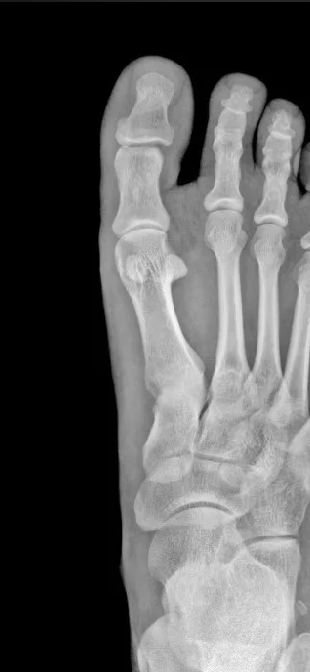

Все изменения хорошо видны на рентгеновском снимке, он и будет первым, а чаще и основным, видом диагностики. Основываясь на рентгенограмме, а также лабораторных показателях, врач выбирает оптимальное лечение и дальнейшее ведение болезни.

На прицельном снимке будут отчетливо видны следующие изменения:

• Суставная щель может быть расширена, в том числе неравномерно, или сужена, в ней обнаруживается выпот или участки обызвествления;

• Суставные поверхности могут не соответствовать друг другу из-за вывиха;

• В тканях кости и надкостницы обнаруживаются участки разрежения, уплотнения, разрастания, воспаления, перелома;

• Утолщение мягких тканей;

• Новообразования, при наличии.